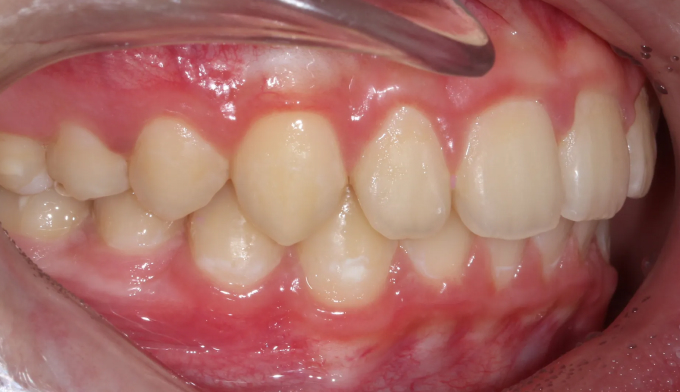

양쪽 송곳니는 일반적으로 같은 시기에 구강내로 맹출합니다.

한쪽 치아만 나오고 다른한쪽은 나오지 않는다면 먼가 문제가 생겼음을 의심해봐야 합니다.

본 케이스에서는 위쪽과 아래쪽 송곳니 모두 치아 머리 주변으로 작은 물혹이 감싸고 있어 스스로 구강내로 나오지 못하고 있었습니다.